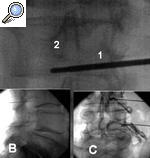

La técnica3 se realiza con el paciente en decúbito prono con una almohada a nivel de la cresta ilíaca para disminuir la lordosis fisiológica. Las proyecciones radiológicas que se emplean para realizar este tipo de bloqueo son similares a las que se han comentado en la región cervical. La primera es una proyección anteroposterior para localizar el nivel a tratar; luego se ha de eliminar el doble contorno del platillo inferior, por lo que se realiza una angulación sagital. Con el Rx en oblicuo, se proyecta la apófisis espinosa hasta la parte medial de la articulación facetaria contralateral (fig. 2A). Con una proyección lateral (fig. 2B), se comprueba que la aguja se deposita en el cuadrante posterosuperior del agujero. Por último se realiza una proyección anteroposterior para comprobar la localización final de la punta de la aguja (fig. 2C). El punto diana en este bloqueo se sitúa 1 mm por debajo del pedículo.

Figura 2. A: proyección oblicua que permite localizar la figura del “perrito”. Nótese la varilla (1) que indica el punto de entrada, 1 mm por debajo del pedículo (2). B: proyección lateral donde se puede ver la localización de la aguja en el cuadrante posterosuperior del foramen. C: proyección anteroposterior donde se ve la salida de las raíces tras la inyección del contraste.